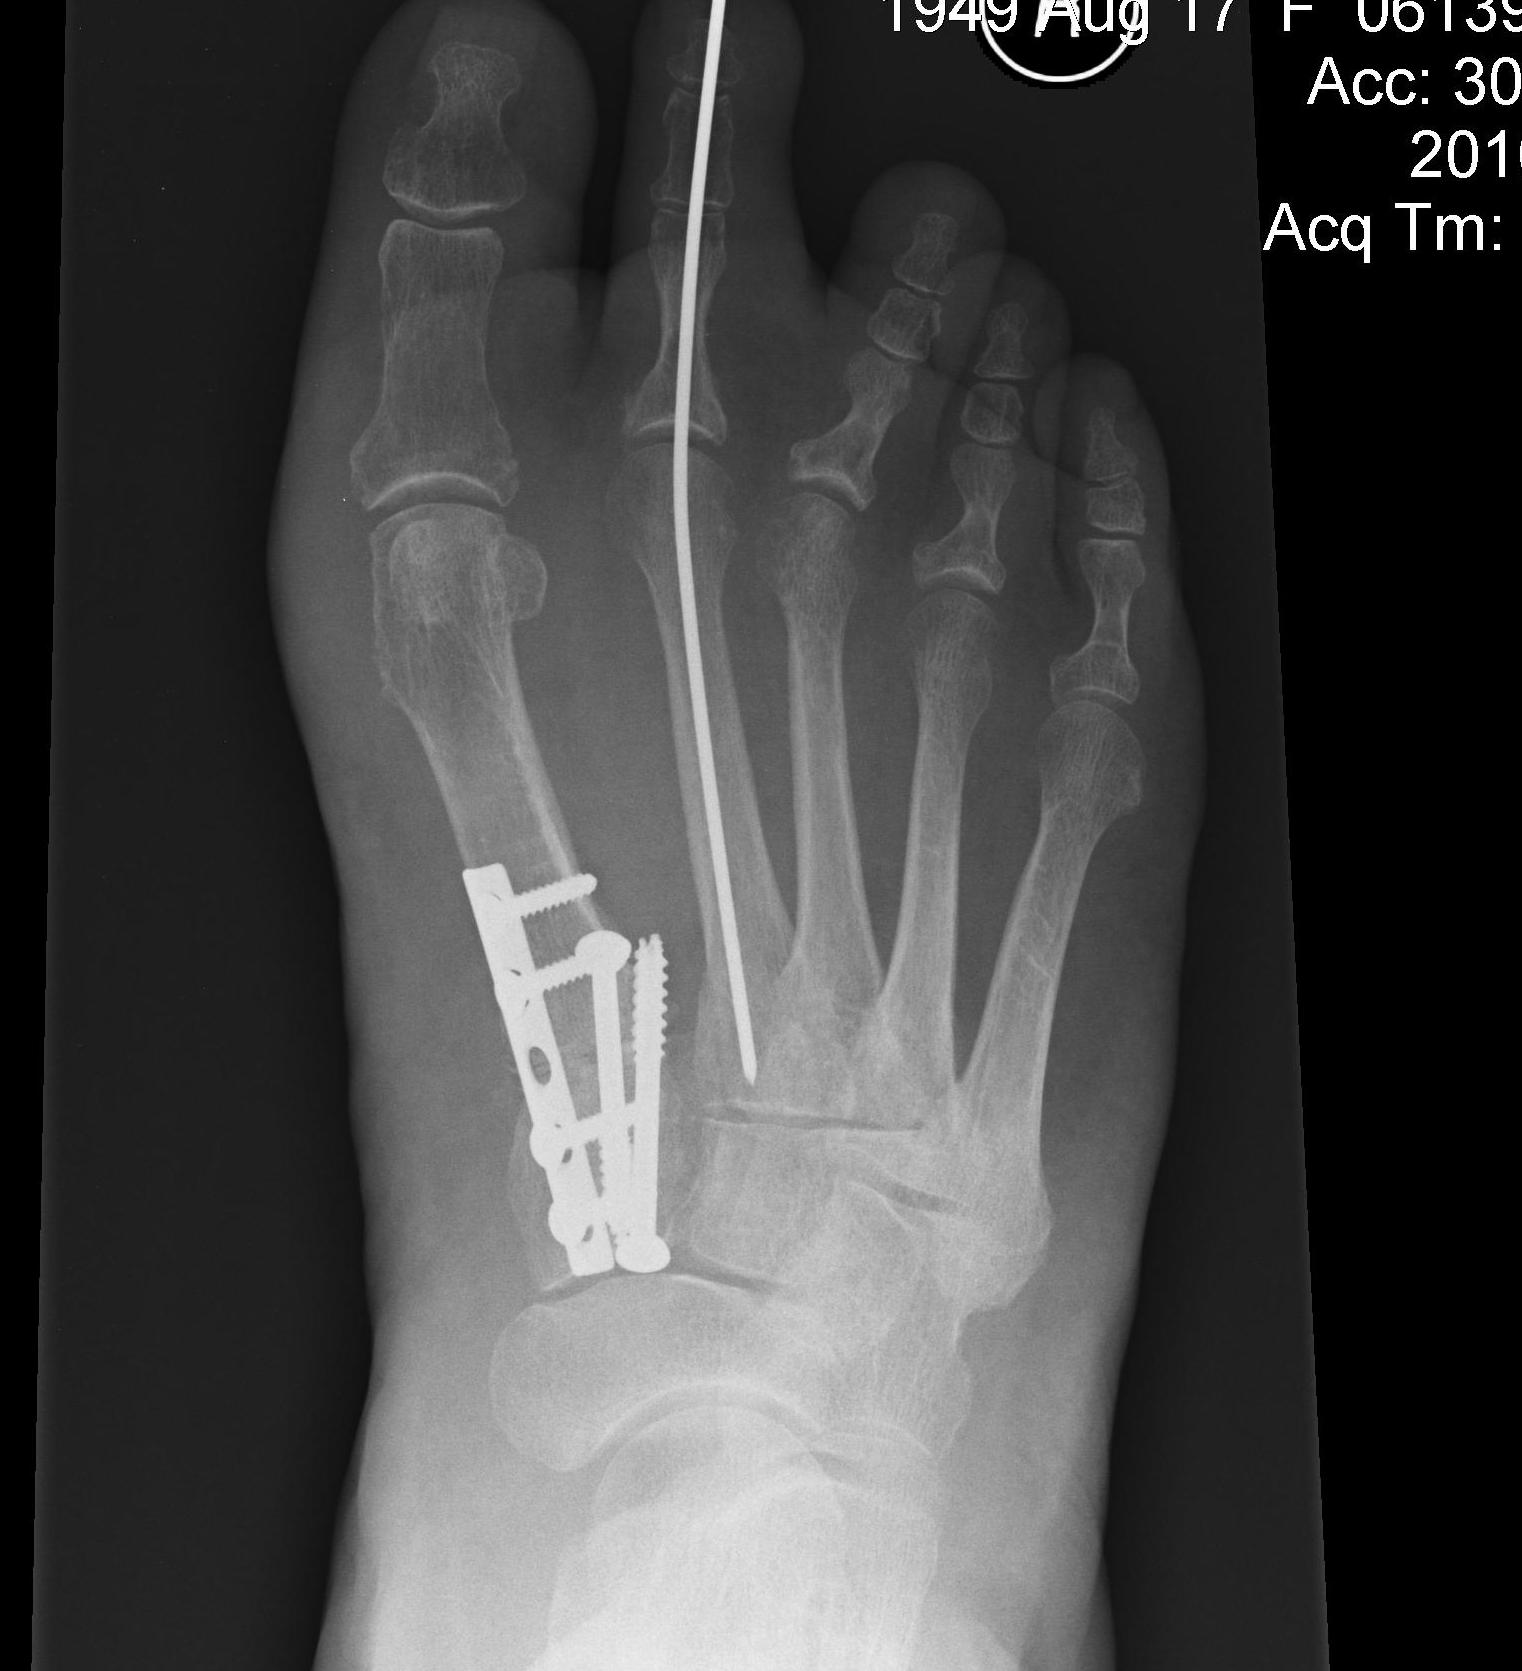

Lapidus Procedure / TMT arthrodesis + DTSP

Indications

- moderate to severe HV

- TMTJ hypermobility

- metatarsus primus varus

Technique

Triplanar correction - coronal / sagittal / rotational

Fixation

- screws / plate / screws + plate